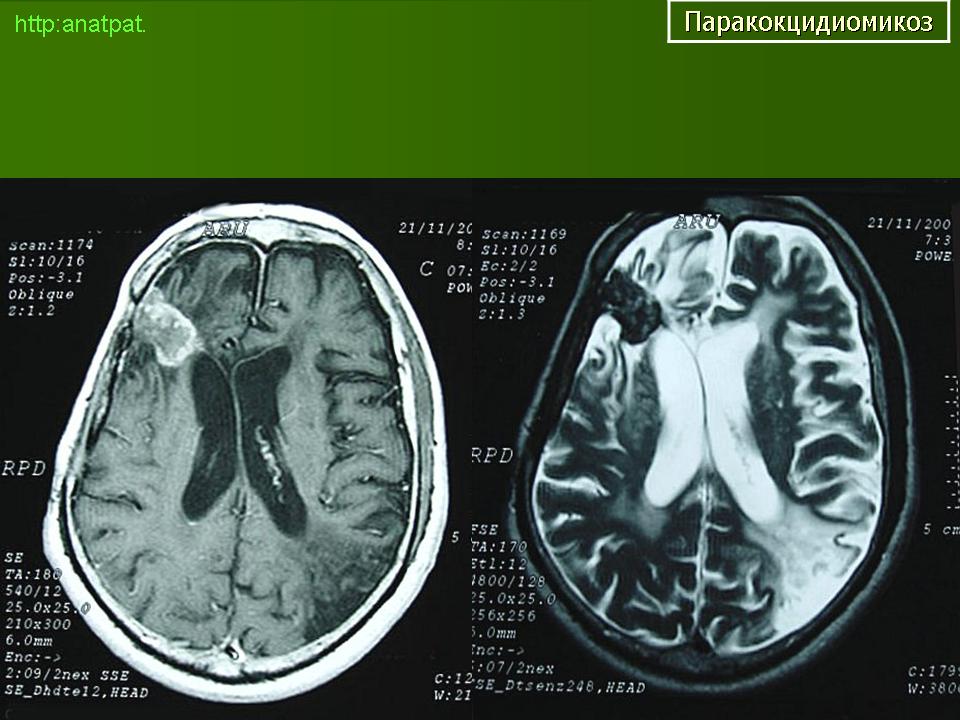

ГМ. Паракокцидиомикоз. +

Паракокцидиомикоз.

Множественные "узловые образования" имитирующие метастазы.